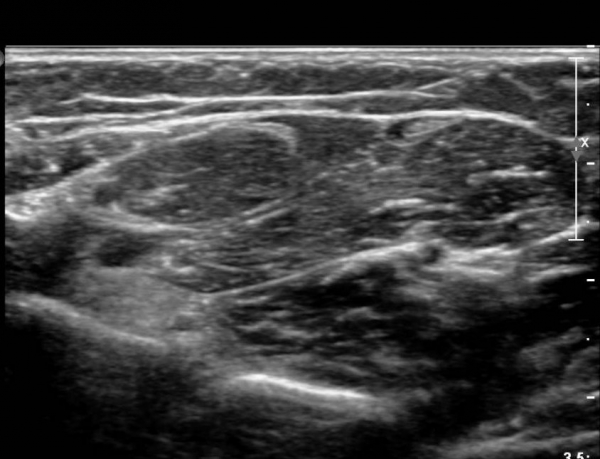

ŽÃËÀÚ¸¦ »ó¹ÚºÎ ¸»´ÜÀ¸·Î  ¿Å°Ü ÆÈ²ÞÄ¡ ºÎÅÍ ±ÙÀ§ºÎ·Î À̵¿ Çϸ鼭 Á¤Á߽Űæ Ⱦ´Ü¸é°Ë»ç¸¦

½ÃÇàÇÏ¿´´Ù(»çÁø 2).  ÆÈ²ÞÄ¡ ÁÖ¸§  ¾à  3cm ±ÙÀ§ºÎ¿¡¼­ Á¤Á߽ŰæÀÇ ÀϺΠ´Ù¹ß(fascicle)ÀÇ Àú¿¡ÄÚ ºÎÁ¾ÀÌ

°üÂûµÈ´Ù(»çÁø 3 , 4,  5,).